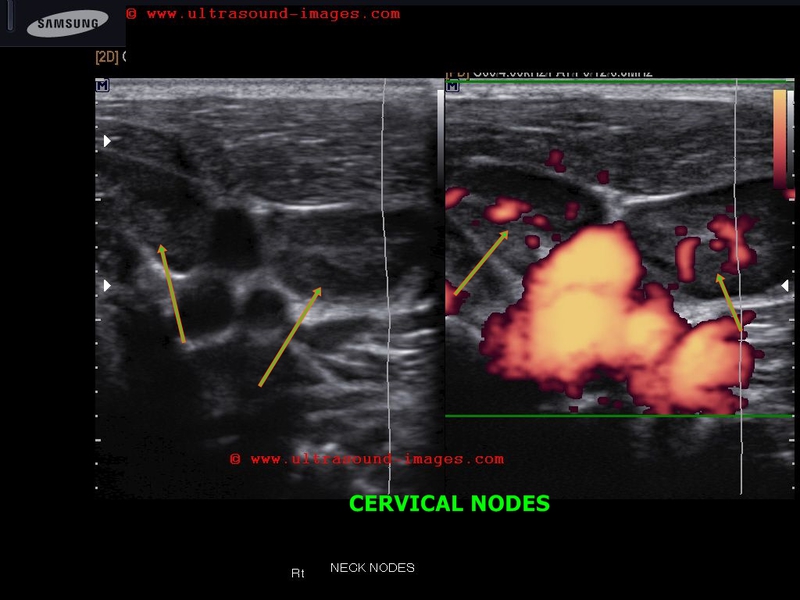

This child shows multiple cervical lymph nodes which show "reactive changes" or changes of lymphadenitis due to Kochs or tuberculous lymphadenitis.

Features seen here include:

- enlarged cervical nodes

- hypoechoic nature of the nodes

- prominent hilar vascularity

Tuberculous lymphadenitis is a common finding and a very common cause of neck swellings in the pediatric age group in developing countries.